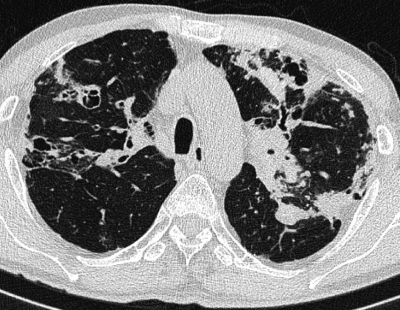

45 歳の男性。喀痰を主訴に来院した。1年前から茶褐色の細長い粘稠な痰をしばしば喀出するようになった。小児期から喘息で治療中である。胸部エックス線写真の正面像と側面像及び肺野条件の胸部 CTを別に示す。